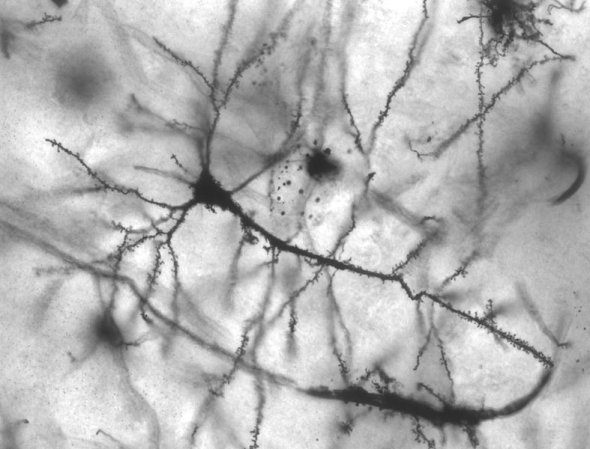

The Popular Science Guide To Neuroscience

Science

By Joey Carmichael